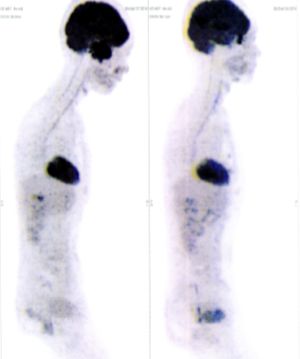

CASE NO: 2 (HEPATOCELLULAR CARCINOMA)

A 40+ man with hepatocellular carcinoma, an incurable cancer. After 2 treatment, the activity of the hepatocellular carcinoma is less.

CASE NO: 2 (HEPATOCELLULAR CARCINOMA) - After a few more treatments

After another few treatment, the activity of the hepatocellular carcinoma is much less. The patient never came back for further treatment, but this case, and case no: 1, shows that incurable hepatocellular carcinoma, often seen in hepatitis B and C patients, can be cured.